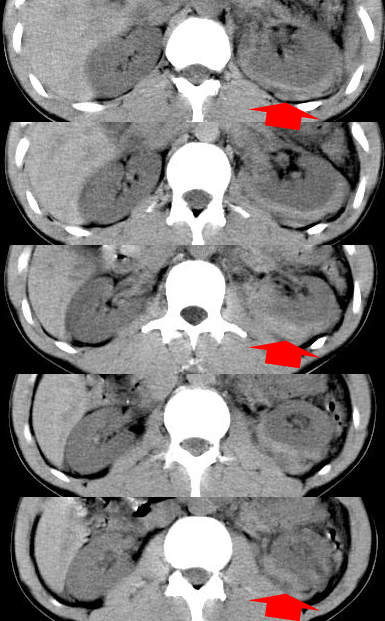

顺便请各位老师认真看看7号片

各位老师觉得胆囊是不是有点积血。我在原始片看胆囊密度不均,似有小液平面

再有就是支持楼主,胆囊7日片比5日片不仅增大许多,靠后下更见液液分层,应该是有积血。

结果收到,谢谢楼主,另外反过来看这个地方是不是游离气体影